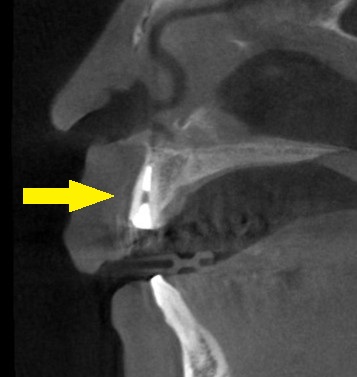

下の写真が手術前後のCTです。